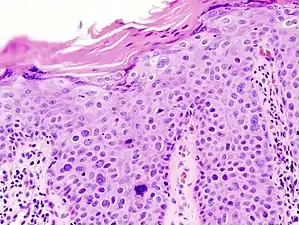

Invasive disease

In invasive cSCC, tumor cells infiltrate through the basement membrane. The infiltrate can be somewhat difficult to detect in the early stages of invasion: however, additional indicators such as full thickness epidermal atypia and the involvement of hair follicles can be used to facilitate the diagnosis. Later stages of invasion are characterized by the formation of nests of atypical tumor cells in the dermis, often with a corresponding inflammatory infiltrate.[12]

- Superficially invasive cutaneous squamous-cell carcinoma. These lesions often do not show the marked pleomorphism and atypical nuclei of cSCC in situ, but manifest early keratinocyte invasion of the dermis.[12]